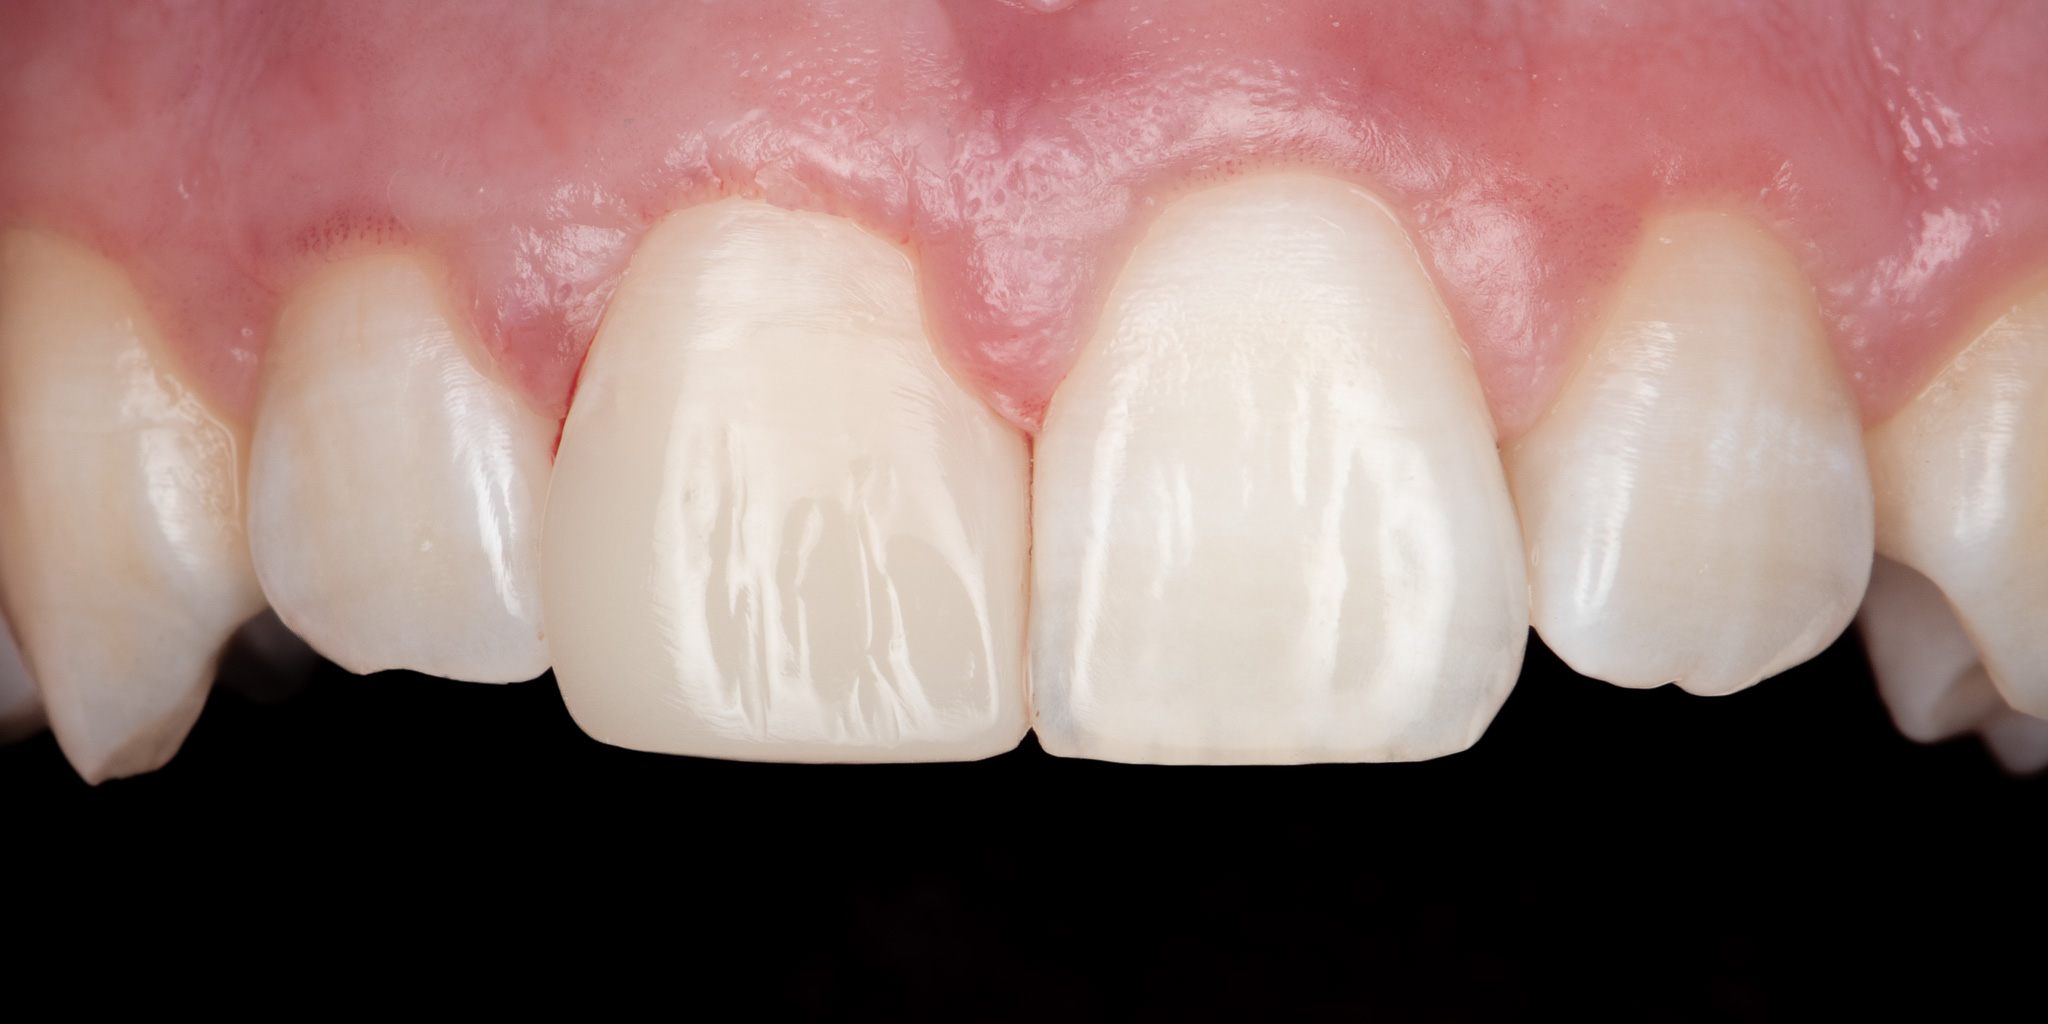

Pacjent zgłosił się podając złamie prawego siekacza centralnego (jedynki) w wyniku urazu. Wykonano estetyczną odbudowę biomimetyczną materiałem kompozytowym 3M™ Filtek™ Universal zapewniającym wysoką estetykę a także podniesioną odporność mechaniczną w porównaniu do konwencjonalnych wypełnień.